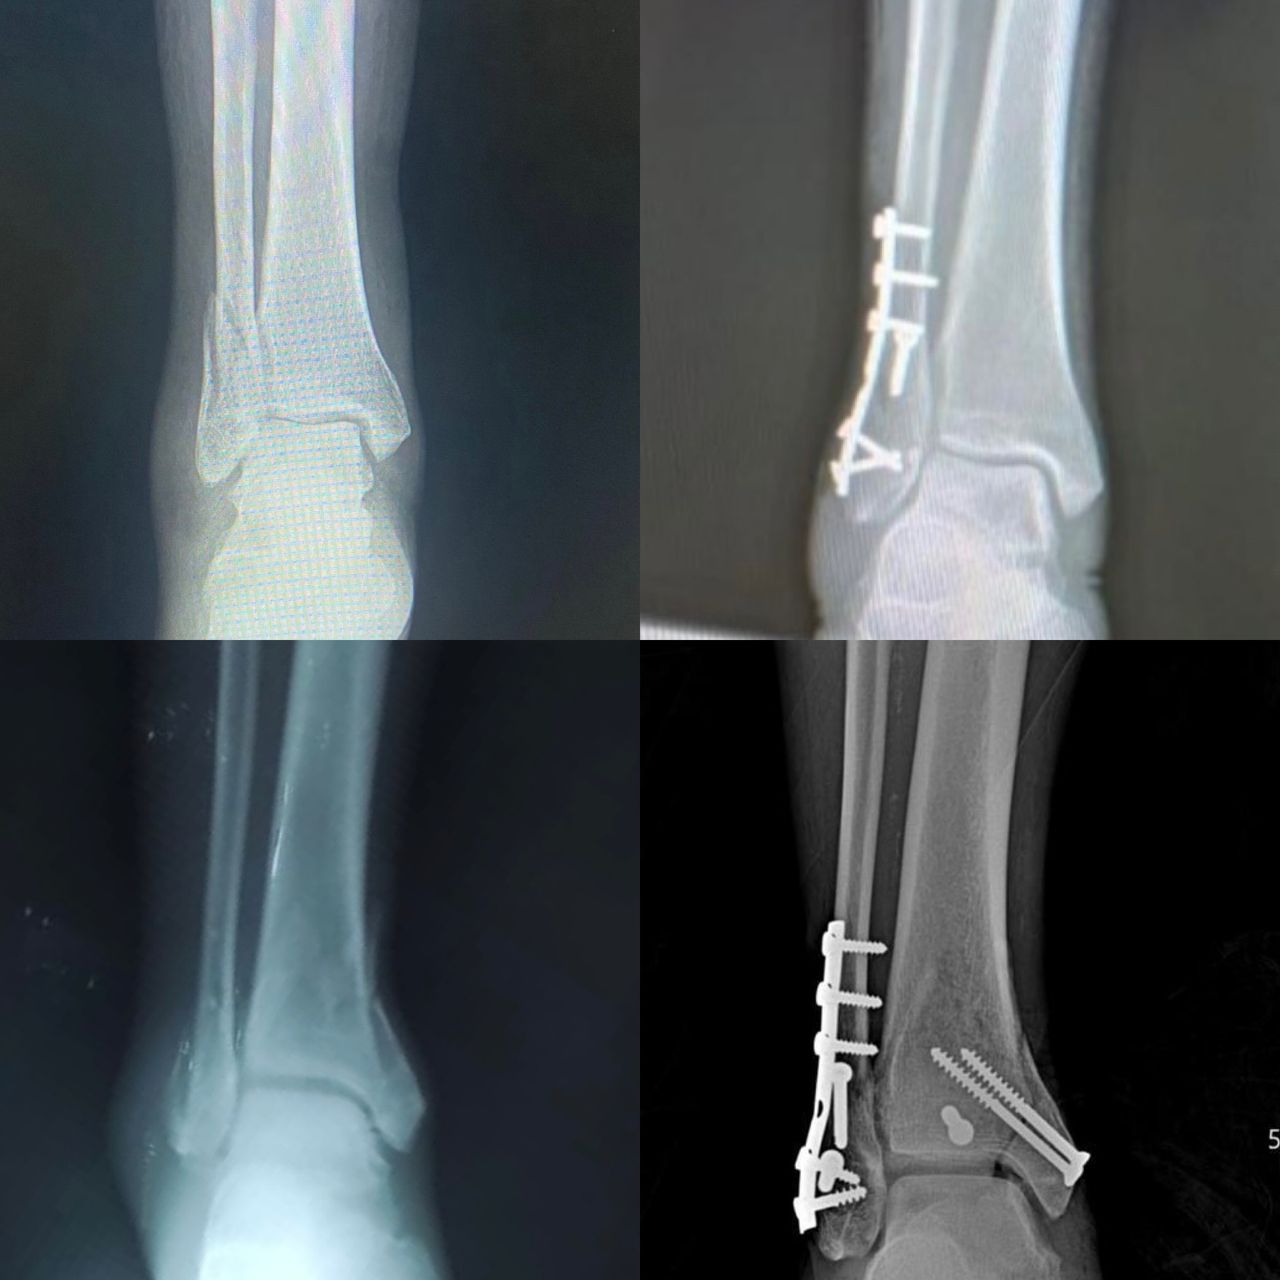

Fotos y videos

El doctor tiene mucha experiencia, muy buena atención y la ayuda de la toma de placas excelente.